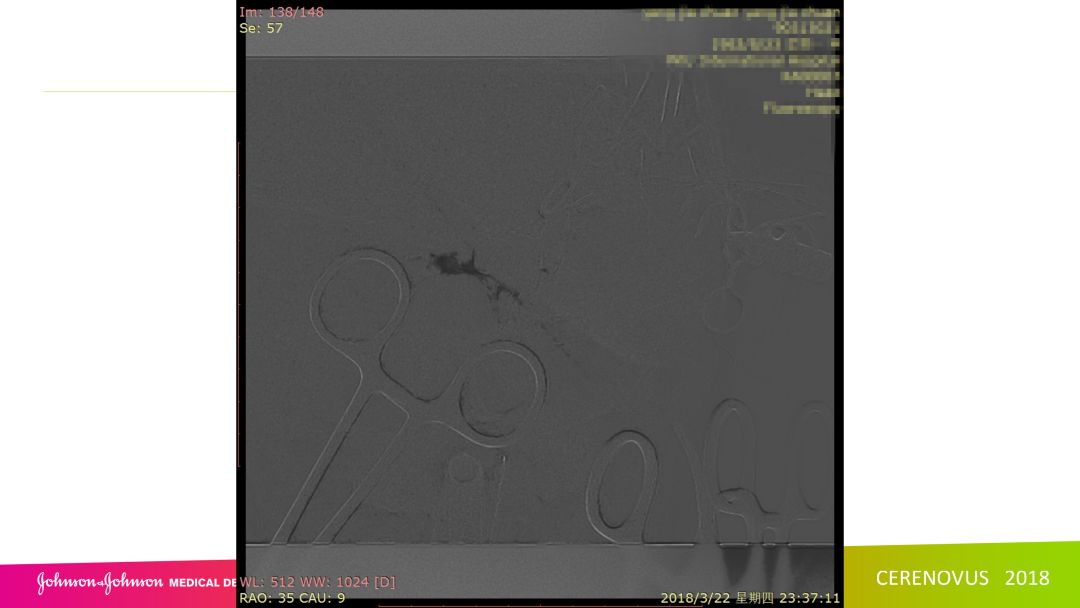

复合手术治疗海绵窦区硬脑膜动静脉瘘一例